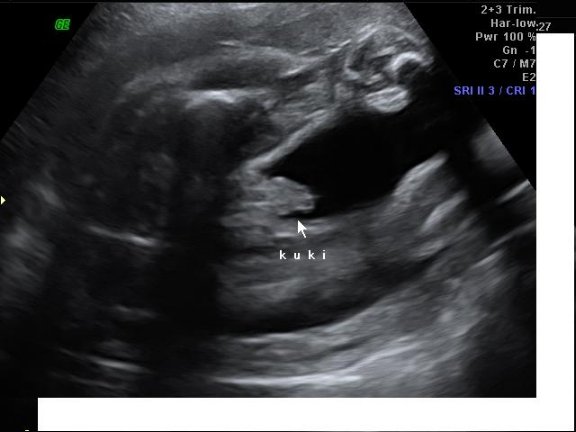

Egy bizonyíték a kukira: Kép

Nagyon szép lett Milán szobája! Ügyes vagy! A kissrác büszke lesz az anyukájára! :) A 4D-s képek! :):):) Szuperek! Milánnak olyan szép kis arcocskája van, hogy csak csuda! :) Nagyon szép! :)